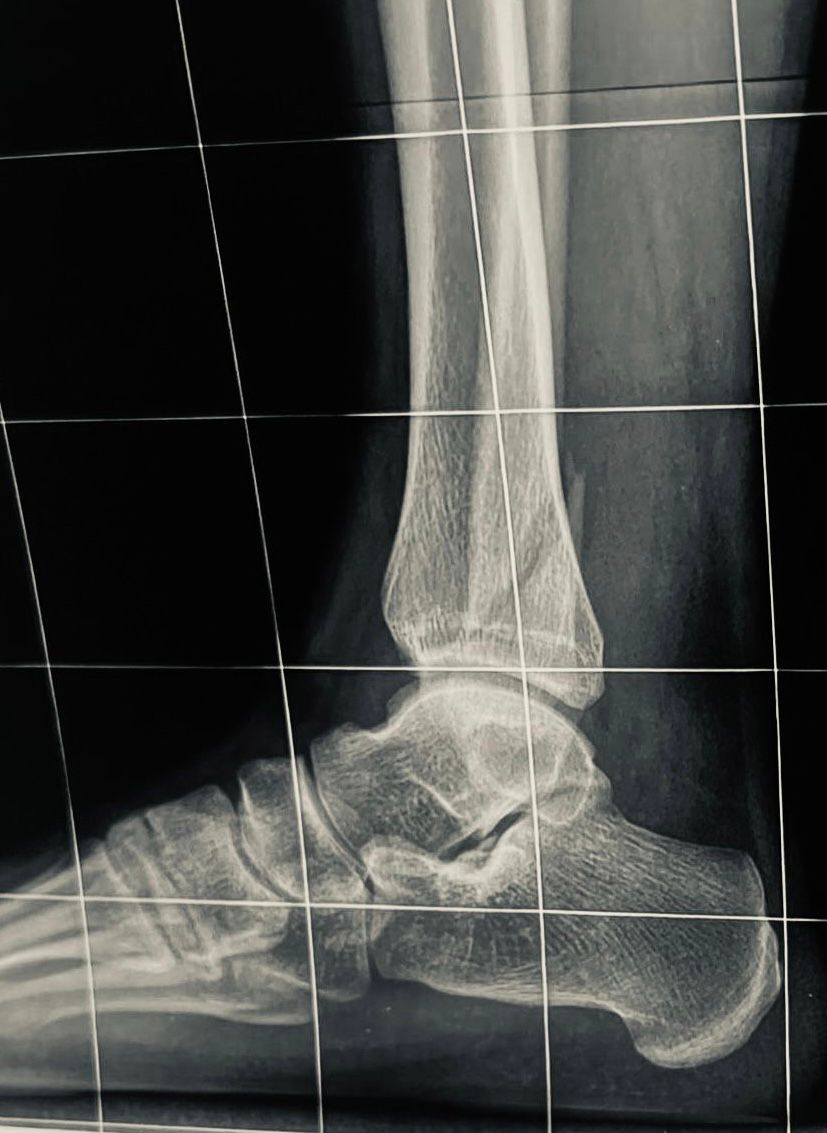

Перелом латеральной лодыжки

Доброго времени суток! помогите определить тактику лечения при данной травме. Достаточно ли обойтись иммобилизацией без хир лечения?

Прямую проекцию и 3/4 можно посмотреть. Если подвывиха нет, можно консервативно. Если разрыв дмс, лучше прооперировать.